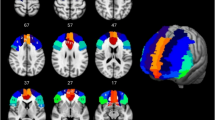

This study examined brain connectivity maps of the four groups of elderly participants at correlation coefficients of 0.5, 0.7, and 0.9. By comparing brain connectivity under different correlation coefficients and frequency bands (alpha1 and alpha2), we analyzed the differences among the high-accuracy/fast group, high-accuracy/slow group, low-accuracy/fast group, and low-accuracy/slow group. The results (Fig. 4) revealed significant differences in brain connectivity in the alpha1 frequency band at a 0.5 correlation coefficient among the high-accuracy/fast, high-accuracy/slow, and low-accuracy/slow groups. Notably, the low-accuracy/fast group had no data at this correlation coefficient.

The findings showed that the high-accuracy/fast group had superior connection strength (thicker lines) and connection density (more lines) compared to the high-accuracy/slow and low-accuracy/slow groups. Specifically, the high-accuracy/fast group demonstrated strong alpha1 connectivity across multiple brain regions, with weaker connections between the right temporal lobe and other brain regions, and no connections on the left side. The high-accuracy/slow group exhibited slightly weaker connection strength and density in the prefrontal region compared to other brain regions, with significantly lower connection density in the left hemisphere compared to the right. The low-accuracy/slow group had lower connection strength and density in both hemispheres compared to the high-accuracy/fast group. Compared to the high-accuracy/slow group, the low-accuracy/slow group had weaker connection strength and density in the right hemisphere but higher connection strength and density in the left hemisphere.

These results suggest that the accuracy of Stroop test measurements is primarily associated with the connection strength and density in the prefrontal and parietal regions of the brain, while the speed of reaction time is related to the central and occipital regions.